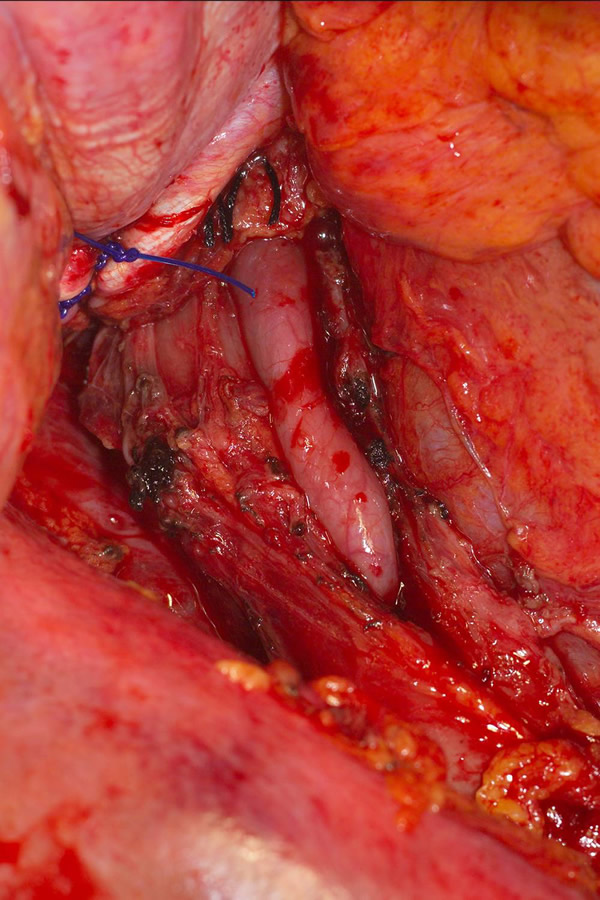

The surgical approach is a left posterolateral thoracotomy, entering the chest over the bed of the unresected 7th or 8th rib. On entering the thoracic cavity, the pulmonary ligament is divided and the lung is packed out of the way superiorly. The epiphrenic diverticulum is often found at the level of the inferior pulmonary vein. The pleura over the esophagus is divided allowing the esophagus to be gently mobilized. Penrose drains are used to encircle the esophagus superior and inferior to the diverticulum to facilitate the dissection (Figure 3). The diverticulum often arises to the right side necessitating rotation of the esophagus to clearly visualize the neck of the diverticulum. The diverticulum and its base are carefully dissected from the adjacent esophagus (Figure 4). Both vagus nerves are clearly identified and preserved during this maneuver. Once the diverticulum base is defined, a 40 Fr bougie is introduced across the gastroesophageal junction. This is performed under direct vision with the surgeon closely monitoring the safe passage of the bougie.